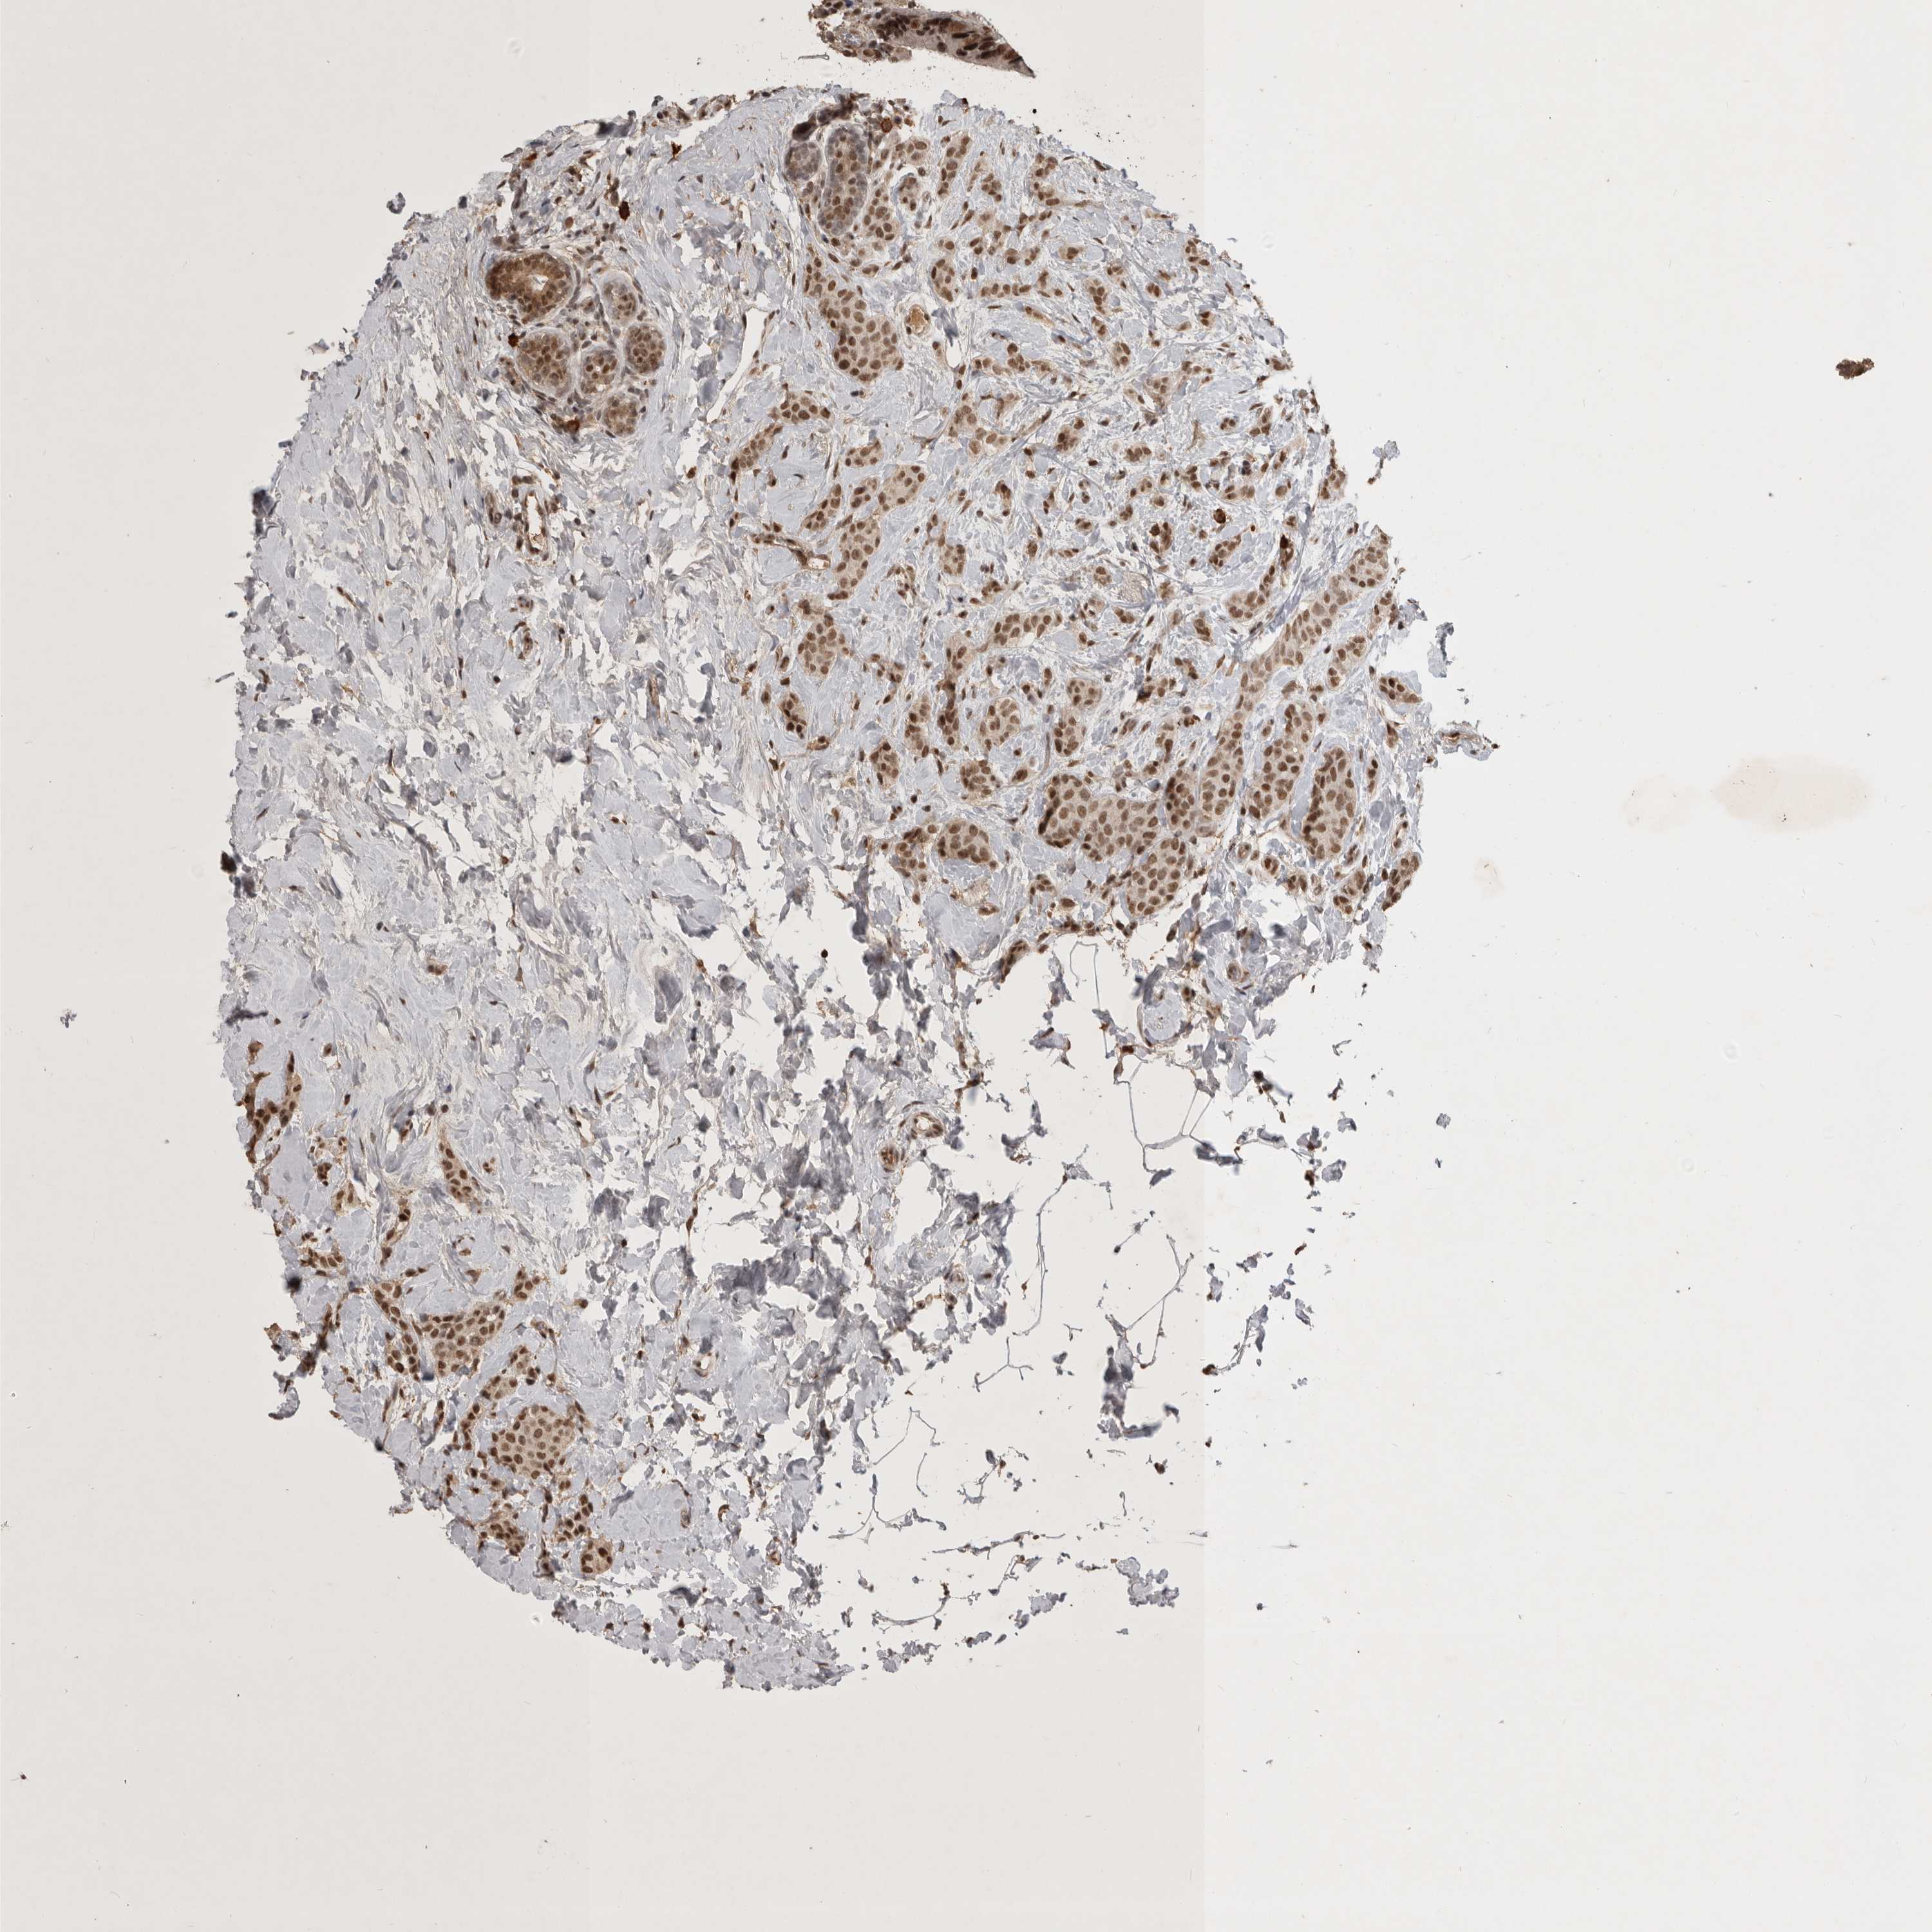

CANCER BREAST CANCER Show tissue menu

BRCA TCGA BRCA VALIDATION PROTEIN EXPRESSION